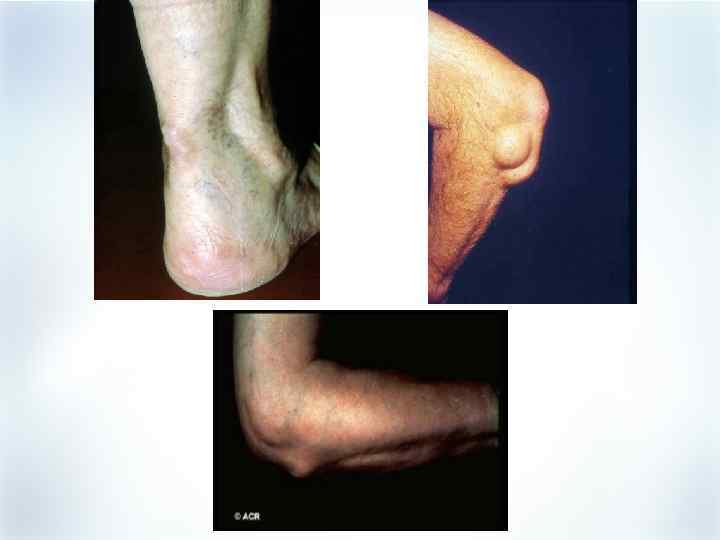

Внесуставные проявления РА § § § § Ревматоидные узелки Сердечно-сосудистые: васкулит, перикардит Легочные: гранулема, интерстициальный фиброз, плеврит Глазные: склерит, ирит Неврологические: компрессионная нейропатия, васкулит Кожные: язва голени, пальмарная эритема Гематологические: гранулоцитопения (синдром Фелти), лейкоцитоз (синдром Стилла взрослых), гипервязкость Почечные/печеночные: нефрит, амилоидоз, гепатомегалия Harris ED Jr. In: Kelley WN et al, eds. Textbook of Rheumatology. 5 th ed. Philadelphia, PA: WB Saunders; 1997: 898– 932. Grassi W et al. Eur J Radiol. 1998; 27(suppl 1): S 18–S 24.

Внесуставные проявления РА § § § § Ревматоидные узелки Сердечно-сосудистые: васкулит, перикардит Легочные: гранулема, интерстициальный фиброз, плеврит Глазные: склерит, ирит Неврологические: компрессионная нейропатия, васкулит Кожные: язва голени, пальмарная эритема Гематологические: гранулоцитопения (синдром Фелти), лейкоцитоз (синдром Стилла взрослых), гипервязкость Почечные/печеночные: нефрит, амилоидоз, гепатомегалия Harris ED Jr. In: Kelley WN et al, eds. Textbook of Rheumatology. 5 th ed. Philadelphia, PA: WB Saunders; 1997: 898– 932. Grassi W et al. Eur J Radiol. 1998; 27(suppl 1): S 18–S 24.

Внесуставные проявления при синдроме Фелти § § § § § Ревматоидные узелки – 75% Потеря веса – 70% Синдром Шегрена – 55% Лимфоаденопатия – 35% Язва голени – 25% Плеврит – 20% Кожная пигментация – 15% Нейропатия – 15% Эписклерит – 10%

Внесуставные проявления при синдроме Фелти § § § § § Ревматоидные узелки – 75% Потеря веса – 70% Синдром Шегрена – 55% Лимфоаденопатия – 35% Язва голени – 25% Плеврит – 20% Кожная пигментация – 15% Нейропатия – 15% Эписклерит – 10%